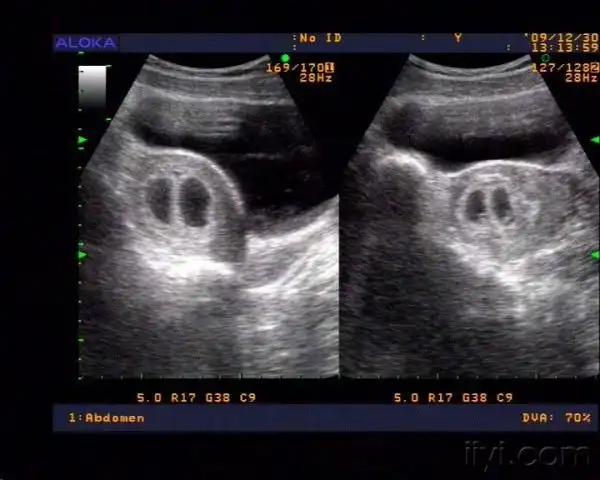

6周 6 胎心胎芽都有了!而且分裂成同卵双胞胎

50天早孕双胎妊娠(双孕囊)